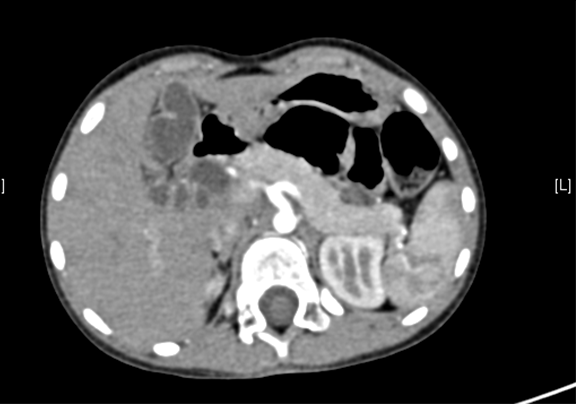

术前CT检查:

静脉期

一般情况:CH-001-CBD-000021,3岁足月产女性患儿,身高105cm,体重16.5kg,

主诉:发现胆总管扩张1月。

现病史:,患儿无明显诱因出现腹痛,无发热不伴有黄疸,在当地医院考虑"胆管扩张症",给予抗炎保守治疗好转。近一个月来患儿未出现腹痛等不良主诉,今日为求进一步诊断来我院,拟诊"先天性胆管囊肿"收入院。

腹部B超:先天性胆总管囊状扩张上腹部CT(外院):胆总管囊肿。